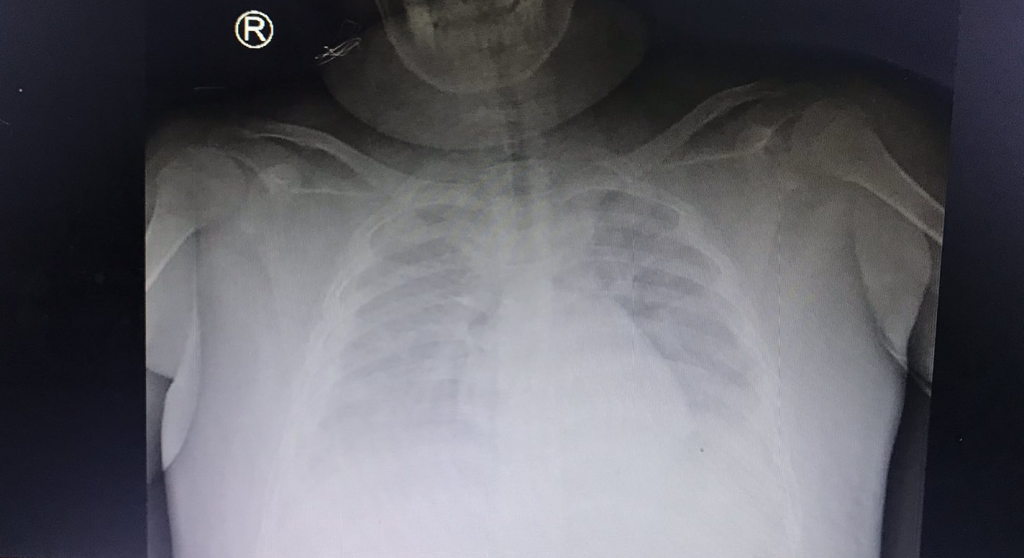

ại đây ghi nhận, trẻ tỉnh, vẻ đừ, sốt 38.4 độ, môi hồng, SpO2 94%, chi mát, mạch quay bắt nhẹ 135 lần/phút, tim đều rõ 135 lần/phút, HA kẹp: 110/90 mmHg, nghe mờ, thở đều êm 20 lần/phút, bụng mềm, gan 3 cm dưới hạ sườn phải, petechie rải rác toàn thân. Xét nghiệm Hct khẩn: 44%, tiểu cầu 32 000/microL, men gan tăng AST/ ALT: 543/ 286 đv/L, xét nghiệm Dengue IgM: dương tính PCR SARS-COV2 dương tính. Siêu âm ổ bụng: tụ dịch dưới bao gan, phù nề túi mật, dịch tự do ổ bụng, tràn dịch màng phổi 2 bên lượng ít, nên được Chẩn đoán: Sốc sốt xuất huyết Dengue Ngày 5 và Covid 19 ở trẻ dư cân, béo phì.

Trẻ được xử trí: thở oxy truyền dịch chống sốc. Tình trạng sốc không cải thiện được đổi sang dung dịch cao phân tử dextran dưới hướng dẫn của đo huyết áp động mạch xâm lấn, áp lực tĩnh mạch trung tâm CVP, điều trị thuốc kháng virus. Diễn tiến trẻ tiếp tục biểu hiện sốt, sốc kéo dài suy hô hấp, tràn dịch màng phổi màng bụng lượng nhiều gây chèn ép, được tiếp tục chống sốc, truyền dung dịch đại phân tử, điều chỉnh rối loạn đông máu, hỗ trợ gan, điều chỉnh toan chuyển hóa, điện giải, thuốc hạ sốt. kết quả sau điều trị gần 1 tuần tình trạng trẻ cải thiện dần, tỉnh táo. Đây là trường hợp hiếm gặp trẻ vừa đồng nhiễm COVID-19 vừa mắc sốt xuất huyết, gây nhiều khó khăn cho các bác sĩ điều trị vì sốc sốt xuất huyết không có chỉ định sử dụng thuốc chống đông,chống viêm vì có thể gây nguy cơ xuất huyết nhiều hơn.